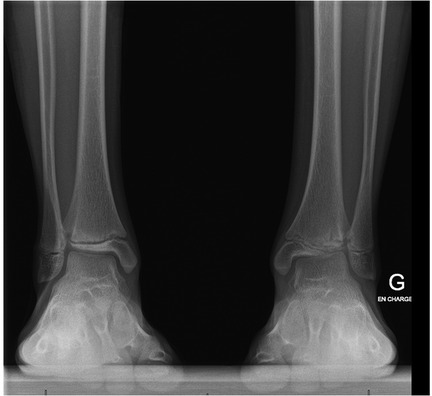

Anamnesis showed no family history of illness, genetic disorders, or osteochondrosis. The patient was 148 cm tall and weighed 37.5 kg, both measurements being one standard deviation above the mean. Clinical exam showed unrestricted, and symmetrical motion in the left ankle. There was a 13 mm leg length discrepancy on the left, and a standing hindfoot valgus angle of 10°. Palpation triggered pain in the joint's anterolateral aspect. Pain was noted over the anterior talofibular ligament with palpation, tension, weight-bearing, and tiptoe walking. The initial x-ray image of the left ankle revealed an irregularity of the distal tibia, with thinning or even an absence of the lateral epiphysis. The physis itself appeared scalloped and was difficult to clearly distinguish on its lateral side. A standing x-ray image of both ankles was taken, and radiographic alignment analysis revealed valgus of the joint line of the left ankle, with a mechanical distal lateral tibial angle measured at 76° (Figure 1). Unexpectedly, we identified trophic disturbances in the distal epiphysis of the contralateral tibia, indicating the presence of bilateral osteochondrosis. Indeed, the right epiphysis appeared to be both atrophic and sclerotic, but without fragmentation. A CT scan confirmed the fragmentation of the left epiphysis and a complete disruption of the physis on its lateral side. In certain instances, the imaging findings were indicative of possible physeal bars (Figure 2). MRI also confirmed the fragmentation and subsequent involution of the distal tibial epiphysis. It also revealed severe focal alterations in the physis and important metaphyseal deformities consecutive to abnormal endochondral ossification, as well as serious structural alterations in the articular cartilage (Figure 3). No lateral ligamentous or syndesmotic instability, nor rupture, was evident. A diagnosis of bilateral osteochondrosis of the distal tibial epiphysis was made, and the patient was prescribed a symptomatic treatment involving a prohibition of any sports activities and temporary immobilization in a left plaster cast for four weeks without weightbearing due to pain.

Figure 1. This bilateral standing x-ray demonstrated a valgus of the left distal tibial epiphysis (a distal lateral tibial angle of 76°). Unexpectedly, we also noted trophic changes in the right tibial epiphysis.